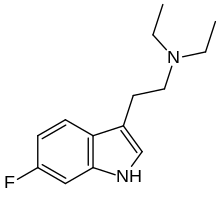

| DET | artificial | H | CH2CH3 | CH2CH3 | N,N-diethyltryptamine | 61-51-8 |

| 2-Me-DET | artificial | 2-CH3 | CH2CH3 | CH2CH3 | N,N-Diethyl-2-(2-methyl-1H-indol-3-yl)ethan-1-amine | 26628-88-6 |